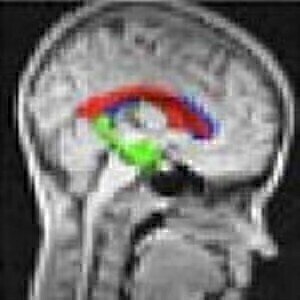

Scientists at the educational institution have developed a new method of scanning using MRI which increases its sensitivity significantly.

The lab product news centres on hyperpolarisation with parahydrogen, a technique developed by University of York researchers and which raises sensitivity levels in MRI scans.

It involves transferring to the scanned molecules the magnetism of parahydrogen, which makes them more visible in the MRI scan.